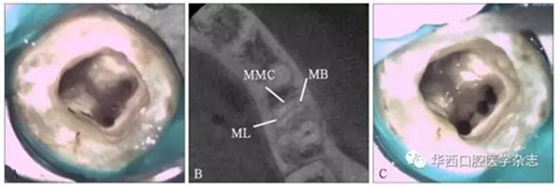

在75顆下頜第一磨牙中,疏通近中三根管的牙齒17顆(22.7%)。肉眼直視下探查分析后確定3個(gè)(4.0%)(圖1),顯微超聲技術(shù)應(yīng)用后探查分析確定14顆(18.7%)(圖2),CBCT分析后顯微超聲技術(shù)輔助下探查分析確定17顆(22.7%)(圖3)。

左:直視下定位MMC(箭頭所示);右:完全預(yù)備后的MMC。

圖 1下頜第一磨牙開髓后直視下探查近中根 顯微鏡 ×16

A:CBCT分析前未探查到MMC 顯微鏡 ×16;

B:CBCT分析顯示近中根三根管;

C:完全預(yù)備后的MMC 顯微鏡 ×16。

圖3 CBCT分析后應(yīng)用顯微超聲技術(shù)輔助探查下頜第一磨牙近中根